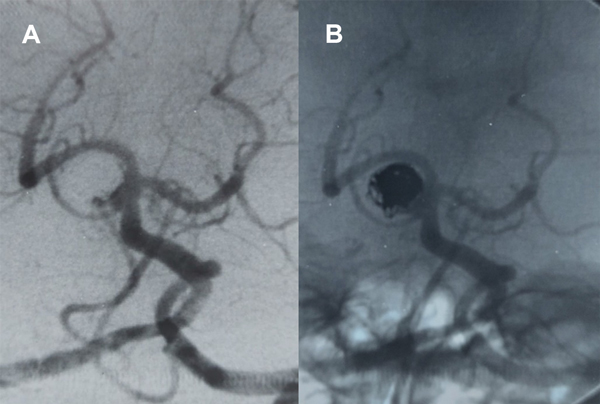

Mujer de 71 años con historia de hipertensión arterial  y aneurismas cerebrales múltiples, tratamiento quirúrgico de aneurisma de comunicante posterior derecho dos meses atrás. Convulsiones tratadas con Levetiracetam. En acuerdo con Neurocirugía se propone tratamiento endovascular de un aneurisma de cerebelosa superior izquierda.

Con la paciente bajo anestesia general  y desde punción femoral bilateral se colocan introductores 6 y 5F.  Se realizan angiografías preembolización desde vertebral derecha dominante demostrando un tope basilar algo displásico. Entre la cerebral posterior y la cerebelosa izquierdas se observa un aneurisma redondeado algo irregular de 3 x 3.5 mm, cuello 3 mm (AR 1.2, DNR 1) desde cuyo margen inferior (proximal) tiene origen la arteria cerebelosa superior. Las cerebrales posteriores están permeables y es visible la comunicante posterior izquierda por inyección desde carótida izquierda.

Se colocan entonces catéteres guías 5F en vertebral derecha y 6F en carótida interna izquierda, planeando un doble abordaje similar al caso 3 presentado arriba, con stenting desde SCA izquierda a segmento P1 izquierdo y microcatéter “jailed” para implantar coils.

Se navega el sifón carotídeo izquierdo y la comunicante posterior y desde ésta en forma retrógrada por cerebral posterior izquierda hacia P1 y tronco basilar utilizando microcatéter SL10 y microguías primero Transend 14 y luego Mirage 0.008” para navegación más delicada, procurando llevarlo a la SCA para implantar un stent Neuroform Atlas.

El SL10 requiere reposicionamiento ya que el tope basilar dilatado dificulta el cateterismo selectivo de la arteria cerebelosa superior izquierda. Para ello se utiliza además de la guía Mirage el agregado de un microbalón Hyperform desde vertebral derecha que es inflado parcialmente en el tope basilar, para formar una contención lateral que permita al cateterismo selectivo de la arteria cerebelosa.

En estas maniobras de reposicionamiento y abordaje con la microguía hacia el origen de la arteria cerebelosa, se nota en un momento la limitación de movimiento del extremo distal de la microguía que no permite retirarla, observando  una posición fija del extremo distal de la guía. Ante esta situación inusual se realiza una XperCT que muestra el extremo de la microguía externo y posterior a la silueta de la arteria basilar, sin observar signos de disección; en cambio, impresiona que el extremo de la microguía se insinúa en una rama perforante muy delgada.

A pesar de las instilaciones de vasodilatadores desde catéter y microcatéter, la microguía permanece atrapada y no se logra retirar tras unas dos horas de intervención,  por lo que se decide dejarla emplazada en el lugar retirando el microcatéter. Los controles angiográficos muestran sólo irregularidad a nivel del segmento P1 izquierdo e indemnidad del resto de los vasos. La tomografía computada realizada con el angiógrafo descarta extravasación.

La paciente se recupera de la anestesia somnolienta, movilizando los cuatro miembros y con respuesta verbal y se traslada a Cuidados Intensivos. Controles posteriores con TAC helicoidal no demostraron infarto (figura 8).

Figura 8. Paciente 18, caso 19. A, B: proyecciones AP y OAD de angiografía convencional y 3D, mostrando un aneurisma tipo BA- SCA izquierdo; C: Fluoroscopía en OAD, abordaje desde PComA izquierda procurando llegar a SCA  izquierda para implante de stent; D: proyección similar en XperCT; E-F: proyección axial de XperCT comprobando situación de microguía fuera de la silueta de arteria basilar, atrapada en vaso perforante.